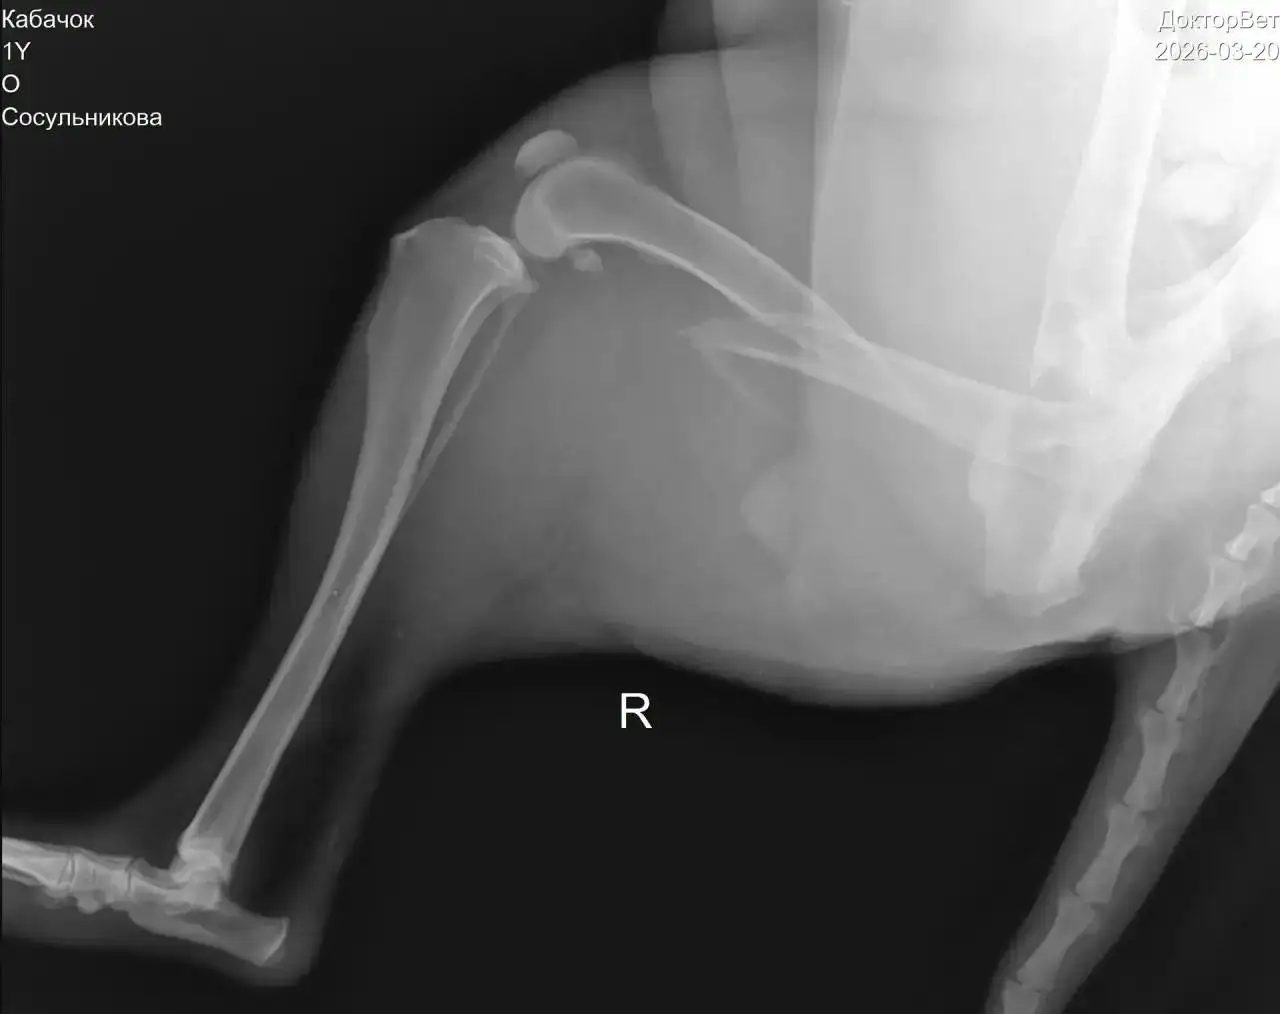

Требуется помощь в сборе средств на операцию для животного (кабачок) после того, как его сбила машина. Диагноз: перелом бедра со смещением. Операция необходима, иначе кости будут травмировать мягкие ткани. Уже собрана часть средств, но требуется дополнительная сумма. Животное находится на передержке с медицинским уходом до операции.